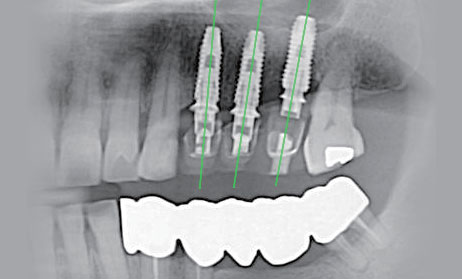

네비게이션 방식을 이용하여,

정확한 길을 찾아줍니다.

네비게이션 임플란트는 최소 절개 수술로 과다 출혈 2차 감염으로 인한 혈압 상승 등의 위험을 줄여 당뇨, 고혈압 등 전신질환 환자에게도 적용될 수 있는 방법입니다.